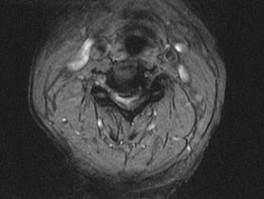

问题 男,65岁,颈部疼痛,双下肢无力3月余,请结合影像学检查,选出最可能的诊断 ( )

选项 A、小关节面综合征 B、椎管狭窄 C、脊膜瘤 D、脊膜膨出 E、脊髓空洞症

答案 B